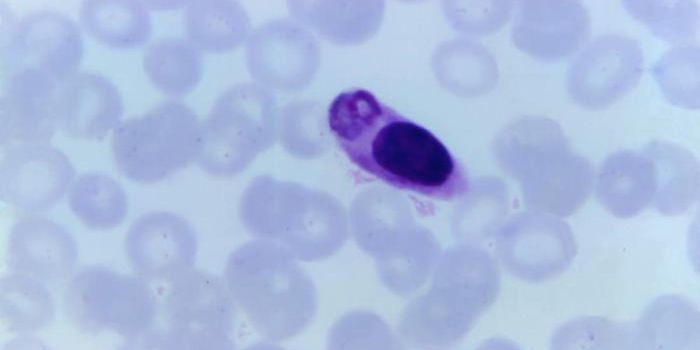

NOV 23, 2021MicrobiologyWhen the parasite Plasmodium falciparium is transmitted from mosquitoes to humans, it causes malaria. So what does it do ...